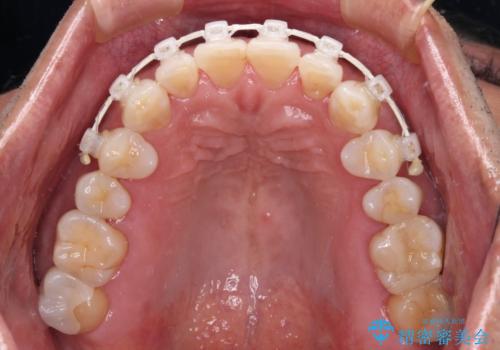

- 矯正装置

- 審美装置

上顎前歯にワイヤー装置を装着し、セラミッククラウンとは干渉しないようにしながら歯列を整えることとしました。